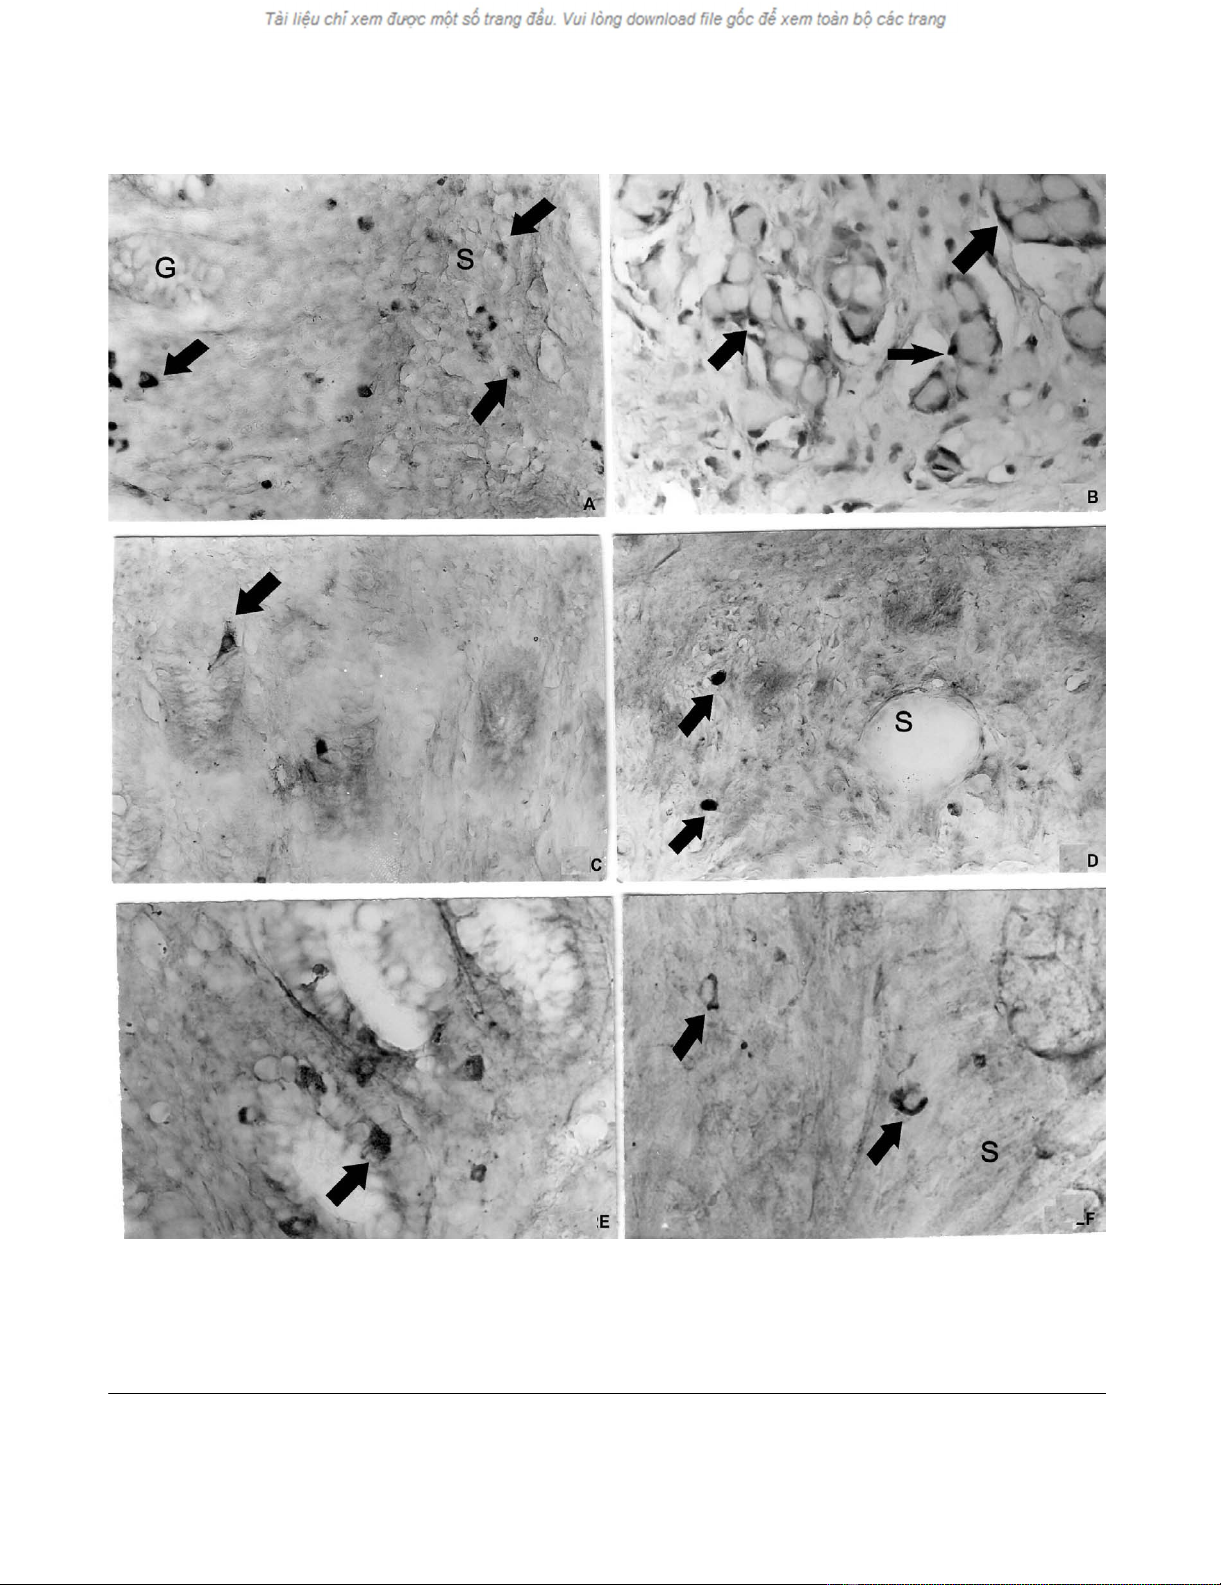

a. Chromogranin A-positive cells (arrows) in the normal appendiceal glands (G) and in submucosa (S)Figure 2

a. Chromogranin A-positive cells (arrows) in the normal appendiceal glands (G) and in submucosa (S), b. Chromogranin A-

positive endocrine cells (arrows) delineate the tumour nests of goblet cells, c. Somatostatin-positive endocrine cells (arrows)

in the normal appendiceal mucosa, d. Somatostatin-positive cells (arrows) in the appendiceal submucosa (S), e. Synapto-

physin-positive endocrine cells (arrow) in the normal appendiceal mucosa, f. Synaptophysin-positive endocrine cells (arrow)

in the appendiceal submucosa (S). Magnifications × a, b, c, d, e, f- × 300.

Light microscopic immunohistochemistry

Dispersed endocrine cells or endocrine cells in nests con-

taining 3–4 goblet cells were observed in the submucous

and muscle layer of the appendix. The endocrine cells in

appendiceal tumour nests were chromogranin A- (Figure

2a,b), somatostatin- (Figure 2c,d), synaptophysin- (Fig-

ure. 2e,f) and serotonin-positive. The endocrine cells,

invading the wall of the caecum were all chromogranin A-

, synaptophysin- and serotonin- (Figure 3) positive. The

endocrine cells in the appendix and caecum tumour sam-

ples were bombesin-, endorphin-, gastrin- and secretin-

negative.